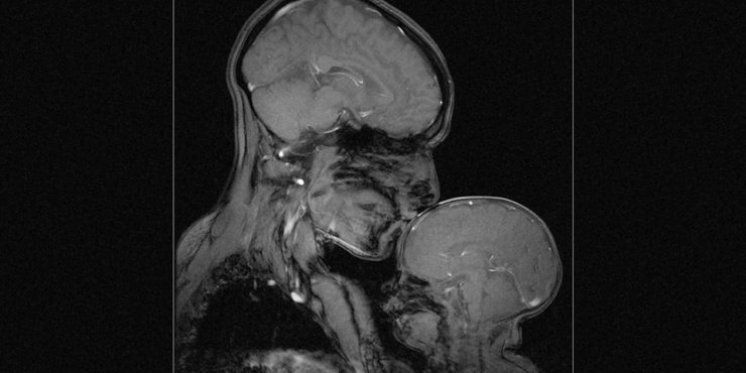

Gledate u prvu sliku magnetske rezonancije (MRI) koja prikazuje vezu majke i djeteta, a koju je snimila neuroznanstvenica Rebecca Saxe. Slika zapravo prikazuje Rebeccu i njezinog dvomjesečnog sina Percyja.

"Ovaj MRI nisam napravila u dijagnostičke svrhe, čak ni u znanstvene. Koliko sam ja upoznata, nitko dosada nije snimio MRI majke i djeteta, a ja sam htjela vidjeti kako to izgleda", objasnila je Rebecca.

Možda najneočekivaniji dio slike je kako se vide razlike između djetetovog i majčinog mozga. Bebin mozak je glatkiji i tamniji jer ima značajno manje bijele tvari. Bijela tvar ili bijela masa sastoji se od glijinih ćelija i mijelina koji prenose signale iz jedne regije u mozgu u drugu i između mozga i nižih moždanih centara, odnosno 'komuniciraju' poruke unutar mozga. Taj nedostatak mijelina gotovo kao da se čini kao stvaran vizualni primjer toga kako majke doslovno oblikuju i formiraju svoju djecu od rođenja. Način na koji govorimo, pjevamo, držimo i igramo se s bebama oblikuje temelje mozga kako dijete raste.

Kao mnoge majke, Rebecca je provela nesrazmjernu količinu vremena gledajući svoju bebu. No, zbog toga jer je kognitivna neuroznanstvenica, za nju je gledanje bebe bilo malo drugačije. Konkretno, provela je mnogo vremena gledajući kako se mozak njezine bebe razvija kroz uređaj za magnetsku rezonanciju. Proučavala je kako je očaravajuće gledati kako dječji mozak odgovara na interakciju s odraslima, kako se krvne žile proširuju u mozgu i kako protječu u odgovoru na pjesme i priče u majčinom glasu.

"Majka i dijete predstavljaju snažan simbol ljubavi i nevinosti, ljepote i plodnosti. No, ja sam neuroznanstvenica i radila sam kako bih snimila ovu sliku, ali također sam i majka u njoj, sklupčana unutar nje, zajedno sa svojim sinom", rekla je Rebecca. Uostalom, slika je fascinantna i prekrasna vizualizacija onoga što ostaje nevidljivo u našem životu, a što je ponekad - najsnažnije od svega!